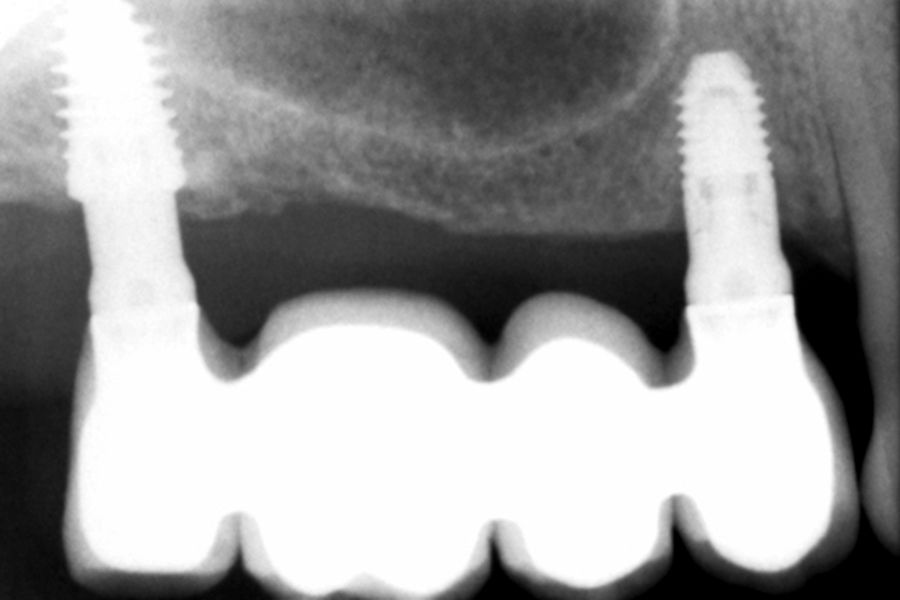

Como primer paso, se realiza un escaneado intraoral de la paciente, para poder generar un encerado virtual con las piezas que queremos rehabilitar con implantes (Figuras 6-8). Esto nos permite planificar con claridad el caso y desde el modelo tridimensional, generar los provisionales y las guías quirúrgicas basadas en la posición protésica, que desde el flujo digital pueden imprimirse (Figuras 9-14). Desde el encerado podemos además generar otras guías, en este caso radiológicas, con las que realizar el Cone-Beam Computed Tomography (CBCT) de planificación. Con esta información tenemos en el mismo estudio radiológico la fusión de nuestra planificación quirúrgica y la posición real de la prótesis adaptada a la oclusión, muy útil para generar una planificación que contempla todos los parámetros. En este caso, se planifican implantes cortos de 6,5 mm en el primer cuadrante, de morfología Core-Xâ, para lograr una correcta estabilidad primaria en un tipo óseo IV como vemos en el corte seccional (Figuras 15 y 16). En el segundo cuadrante, con similares características, planificamos implantes de 6,5 y 5,5 mm de longitud (Figuras 17 y 18).

El fresado de este tipo de implantes, al basarse en la oseodensificación en toda la longitud, se realiza a menor diámetro, en dos tramos, uno para el cuerpo del implante y otro para el ápice, que siempre tiene una mayor capacidad de penetración y menor diámetro. Para una situación de hueso tipo IV/V en el maxilar , fresaremos hasta 2,8 mm en la zona del cuerpo y a longitud de 1,8 mm para el ápice, lo que se corresponde con la fresa piloto. Con ello al insertar el implante generamos una compresión lateral que produce una mayor estabilidad primaria en estas zonas de baja densidad (Figuras 19 y 20). Una vez colocado el implante, todo el hueso que le rodea, circunferencialmente alcanza una mayor densidad, lo que produce que la estabilización sea mayor en toda su superficie (Figuras 21 y 22). Si realizamos una comparativa entre el volumen condensado mediante la colocación de un implante convencional y uno de la morfología Core-Xâ, se observa la diferencia entre el cuerpo del implante y el fresado, lo que nos da una idea de la diferencia en la consecución de la estabilidad primaria (Figuras 23 y 24).

Transcurridos 6 meses desde la carga inicial progresiva, se puede elaborar la prótesis definitiva, trasladando los parámetros de la prótesis provisional (Figura 27). La paciente continúa en seguimiento durante un año, realizándose radiografías de control para el monitoreo del hueso crestal, sin encontrarse pérdida ósea asociada en ninguno de los implantes (Figuras 28-29).